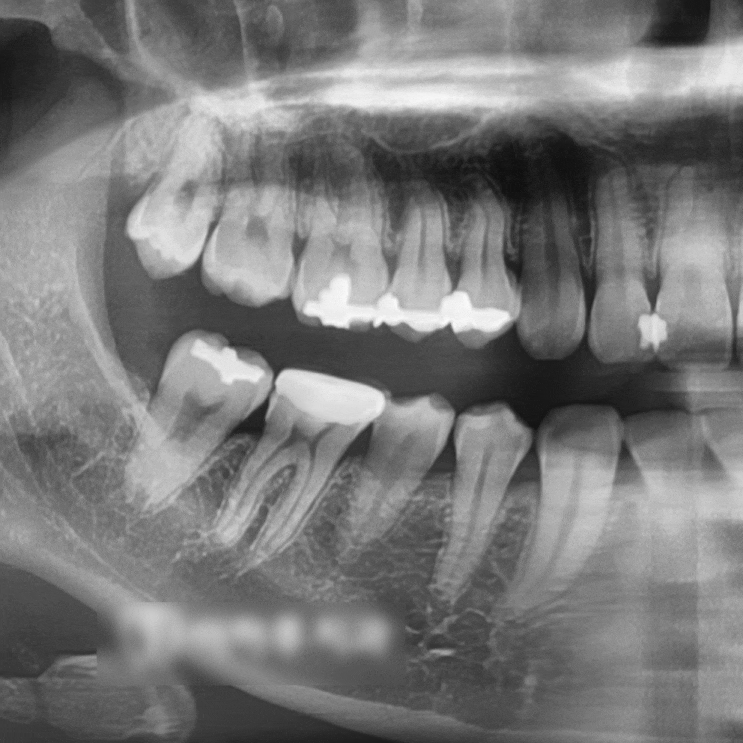

신촌 사랑니 치과 누워있는 매복 제3대구치 발치 신경 손상이 걱정된다면?

안녕하세요, 대표원장 조민기입니다. 많은 분들이 누워 있는 매복 제3대구치 발치 시 신경 손상에 대해 걱...